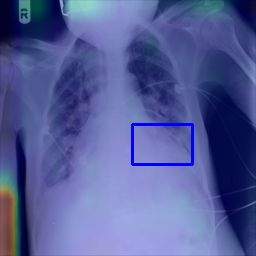

Deployments of artificial intelligence in medical diagnostics mandate not just accuracy and efficacy but also trust, emphasizing the need for explainability in machine decisions. The recent trend in automated medical image diagnostics leans towards the deployment of Transformer-based architectures, credited to their impressive capabilities. Since the self-attention feature of transformers contributes towards identifying crucial regions during the classification process, they enhance the trustability of the methods. However, the complex intricacies of these attention mechanisms may fall short of effectively pinpointing the regions of interest directly influencing AI decisions. Our research endeavors to innovate a unique attention block that underscores the correlation between 'regions' rather than 'pixels'. To address this challenge, we introduce an innovative system grounded in prototype learning, featuring an advanced self-attention mechanism that goes beyond conventional ad-hoc visual explanation techniques by offering comprehensible visual insights. A combined quantitative and qualitative methodological approach was used to demonstrate the effectiveness of the proposed method on the large-scale NIH chest X-ray dataset. Experimental results showed that our proposed method offers a promising direction for explainability, which can lead to the development of more trustable systems, which can facilitate easier and rapid adoption of such technology into routine clinics. The code is available at www.github.com/NUBagcilab/r2r_proto.